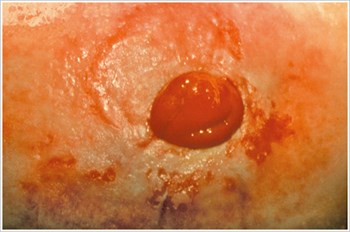

Úlcera de decúbito

Descripción/Causas:

Una úlcera en el área periestomal causada por la presión excesiva del cinturón dispositivo de ostomía, ropa ajustada, placa frontal rígida, hernia periestomal o hábitos relacionados con el trabajo.

Síntomas:

- Dolor

- Úlcera de forma irregular

- Fugas en la bolsa

- Disminución del tiempo de uso